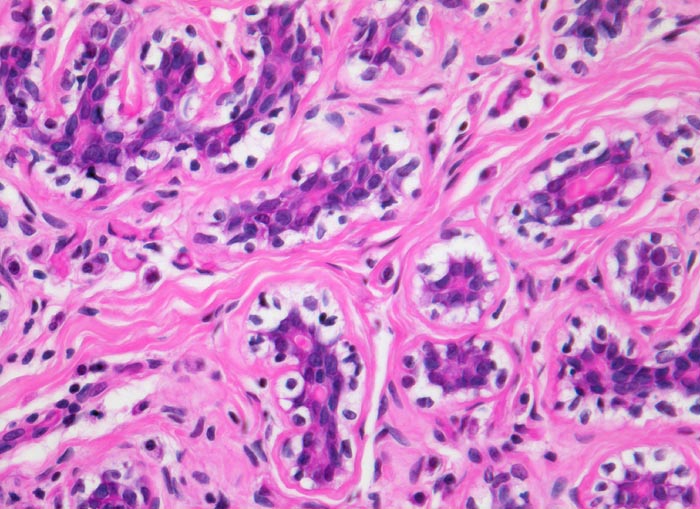

Morphologische Merkmale:

• Multifokale Infiltrate eines invasiv lobulären Mammakarzinoms: Kleine monomorphe, zytoplasmaarme Tumorzellen bilden einreihige Ketten (gänsemarschartig = Indian files) oder sind konzentrisch um nicht neoplastische Drüsen angeordnet.

• Das Karzinom bildet keine Drüsen.

• Zytologisch blande Tumorzellen mit kleinen runden hellen Kernen.

• Reichlich dichtes desmoplastisches Tumorstroma.